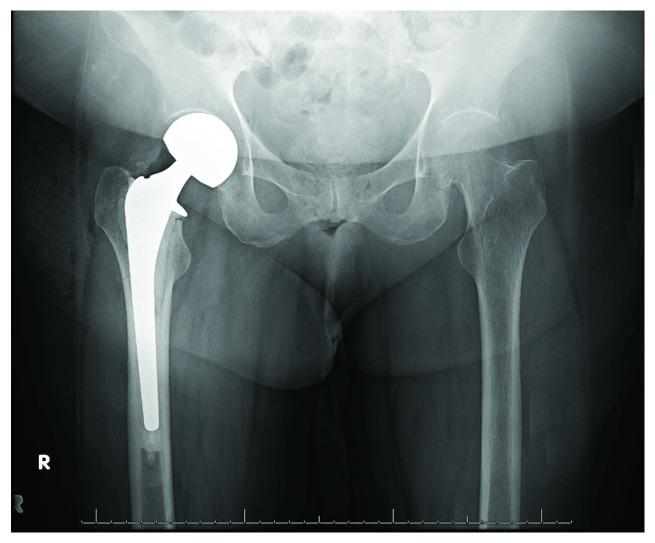

Both hemiarthroplasty and total hip arthroplasty have been well described as effective methods of management for displaced femoral neck fractures in the elderly. Acetabular erosion is a common long-term complication of hemiarthroplasty. We present a case in which rapid acetabular erosion occurs within weeks of hemiarthroplasty, ultimately leading to an acetabular fracture and need for revision to total hip arthroplasty. Early and rapid acetabular erosion following hip hemiarthroplasty has not been well documented in current literature. It may lead to acetabular fracture and may be secondary to infectious causes. If encountered, an infection workup should be initiated.

半髋关节置换术和全髋关节置换术均已被充分描述为治疗老年人移位型股骨颈骨折的有效方法。髋臼侵蚀是半髋关节置换术常见的长期并发症。我们报告一例半髋关节置换术后数周内发生快速髋臼侵蚀的病例,最终导致髋臼骨折并需要翻修为全髋关节置换术。目前文献中尚未充分记录髋关节半置换术后早期快速髋臼侵蚀的情况。它可能导致髋臼骨折,可能继发于感染原因。如果遇到这种情况,应启动感染检查。